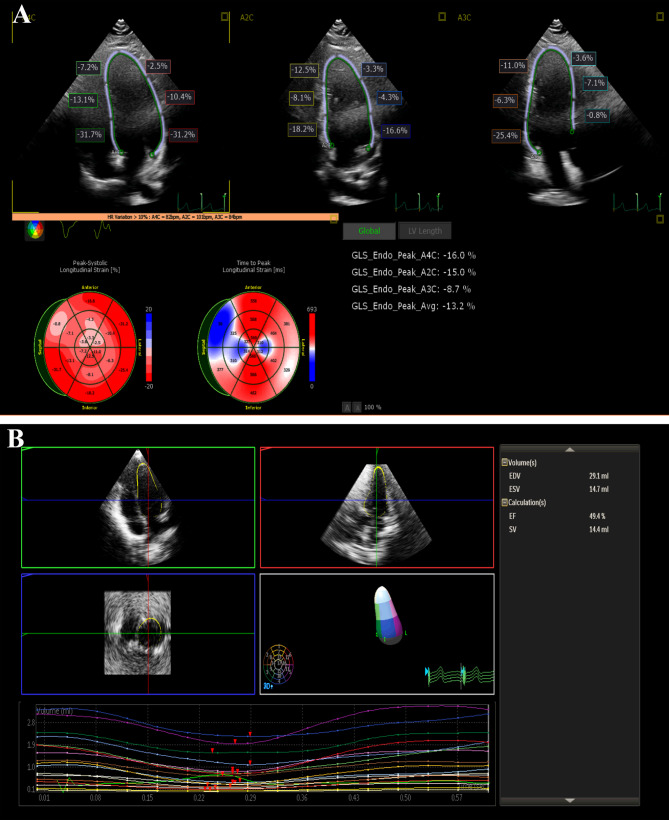

Results: NS patients, whose mean age was 10.93 ± 2.78 years, were subclassified into steroid-sensitive NS (SSNS) 15(37.5%) and steroid-resistant NS (SRNS) 25 (62.5%). Compared with controls, there was no significant difference regarding conventional ejection fraction (EF) or E/A ratio. However, E/E' ratio and tissue Doppler Tie index were significantly higher in NS ( p = 0.001, p= < 0.001, respectively), particularly SRNS. Average global longitudinal strain (GLS) was significantly lower in NS (p = < 0.001), especially SRNS, while 3D ECHO-measured EF significantly declined in NS (p = < 0.001). Tei index and E/E' were moderately correlated with current cholesterol level, while E/E' and GLS correlated with initial serum albumin. On regression analysis, current cholesterol and initial serum albumin were significant predictors for E/E';  p= 0.019 (ß: 0.014, 95% CI: 0.003-0.26) and  p= 0.003 (ß:-1.41, 95% CI: -2.28- -0.53), respectively. No significant factors predicted GLS or 3D EF.

Conclusion: In addition to diastolic subclinical LV dysfunction in children with primary NS detected using Tissue Doppler, systolic alterations could be detected using 2D speckle tracking or 3D ECHO. Some of the resultant subtle LV-impaired parameters could be correlated to NS-related biochemical changes.